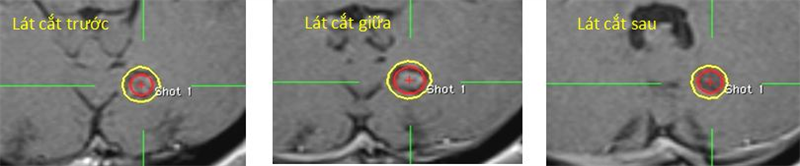

Hình 17: Hình ảnh đặt đường đồng liều 25% đánh giá liều tới hạn

Bệnh nhân Nguyễn Thị Thanh H.; nữ, 66 tuổi. Chẩn đoán: U màng não xoang hang (T). Chỉ định: xạ phẫu dao gamma quay (RGK) liều 16Gy”

Đường màu vàng chỉ đường đồng liều 50%, hình mũi tên chỉ dây giao thoa thị giác không bị ảnh hưởng bởi đường đồng liều màu xanh 25%